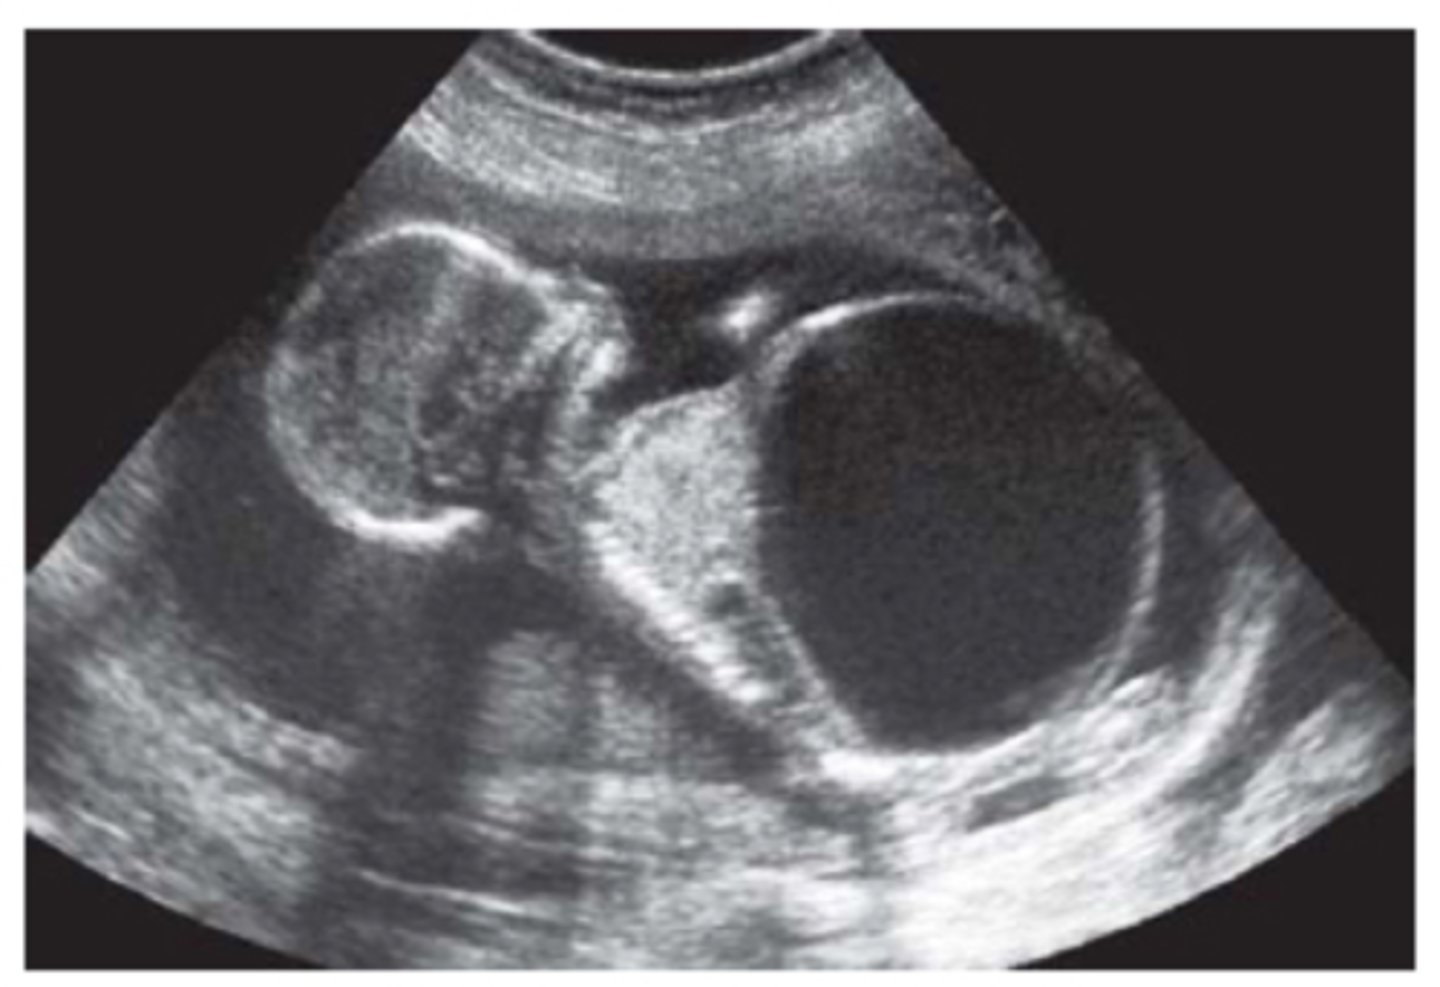

Potter's Syndrome Type II - Multicystic Dysplastic Kidney Disease

Kidney tissue is replaced by cysts - multiple and variable in size

Usually unilateral

Enlarged kidneys

Ill-defined walls & parenchyma/pelvis